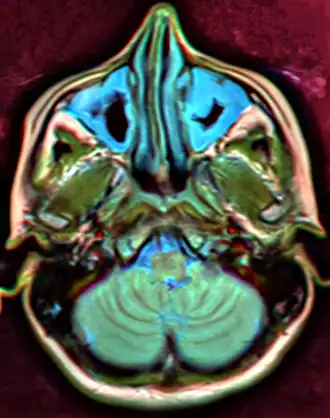

For sinusitis lasting more than 12 weeks, a CT scan is recommended.[66] On a CT scan, acute sinus secretions have a radiodensity of 10 to 25 Hounsfield units (HU). In a more chronic state, they become more viscous, with a radiodensity of 30 to 60 HU.[69]

-

MRI image showing sinusitis. Edema and mucosal thickening appear in both maxillary sinuses. -